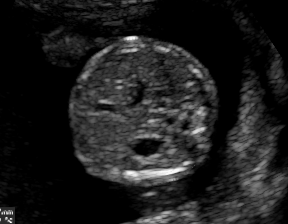

We demonstrate the practical applicability of our method on a challenging medical application, the classification of standardized fetal ultrasound (US) views during prenatal screening. In many countries, US imaging is clinical routine for prenatal health care. The classification of standardized views is important for a consistent, cross-institutional identification of possible abnormalities [47]. Early detection of pathological development can inform following treatment and delivery options [55, 25]. DNNs have shown promising performance to support this task [2]. However, ultrasound images are often hard to interpreted [40]. Anatomical structures have inconsistent appearance [2] and contain different orientations and shapes of anatomical landmarks [1]. Labeled training data is often insufficient as annotating medical images requires significant expertise and is prohibitively expensive in both time and labor. Manifestation of acoustic shadows [17, 44] as shown in Fig. 2(a) as well as different imaging devices as shown in Fig. 2(b) can lead to a domain shift problem for vanilla DNN classifiers. Exploring domain adaptation in fetal US enables DNN classifiers to be effectively utilized on a wider range, which supports identification of abnormalities from varying data sources. This can benefit prenatal healthcare.

We evaluate the proposed method on two fetal US standard plane classification tasks, where the domain shifts are respectively caused by shadow artifacts (Fig. 2(a)) and different image acquisition devices (Fig. 2(b)). For both tasks, images from source and target domains are unpaired and collected independently. We show the key results in the main paper and detailed implementation, network architectures as well as more results in the supplemental Appendix.

IV-D Experiments on cross-device fetal US

The previous experiment on fetal US images is supported by data restricted to one US imaging device. Here, we evaluate MIDNet for a standard plane classification task on data from different imaging devices (different device domains). Device A is “GE Voluson E8” which is the same device in Sec. IV-C, which acquired 2D fetal US images. Device B is “Philips EPIQ V7 G” which acquired another images sampled from about 500 2D US examinations with gestational ages between 20-32 weeks (see Fig. 2 (b)). In this experiment, we use four different anatomical standard plane locations with sufficient images in both domains, including Abdominal, Brain, Femur and Lips, which are selected by an 10-year-experienced sonographer. In this experiment, the source domain is set as device A while the target domain is device B. Training data consists of all four standard planes from the source domain as well as Abdominal and Brain from the target domain. We aim to separate anatomical features (categorical features) and imaging device features (domain features) to obtain generalized anatomical features for achieving high performance of standard plane classification on (Femur and Lips). Here, contains Abdominal, Brain, Femur and Lips from the source domain and contains Abdominal and Brain from the target domain. Hyper-parameters to in Eq. 11 are for the proposed MIDNet model and is additionally for MIDNet+.